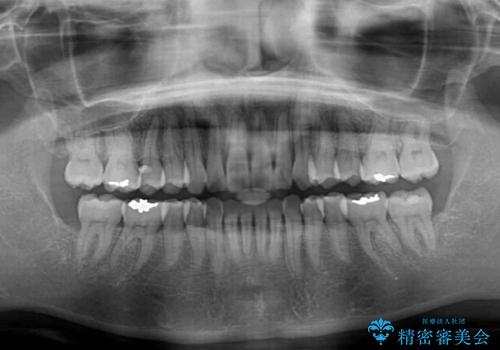

短期間で仕上げたい ワイヤーでの非抜歯矯正

- 前歯の捻れと、それに伴う口元の突出感を気にして来院された患者様です。

早く治療を終えたいとのことで、ワイヤー装置による矯正治療を行うこととしました。

上顎前歯の叢生が解消されると出っ歯になることが分かっていたので、両側奥歯付近にアンカースクリューを入れ、出っ歯を改善するためのゴムかけを行いました。

ゴムかけを頑張っていただいたので、当初の予定通り、1年強で治療を終えることができました。